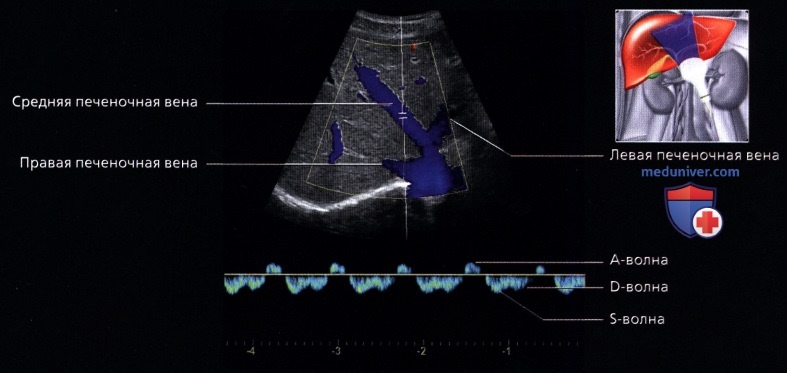

Изранов лекции печень

Изранов лекции печень 112 фотографий